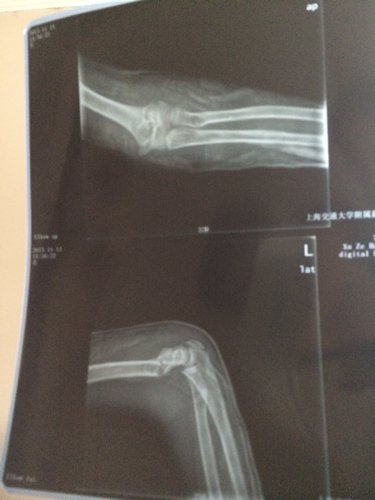

小儿十四周岁,一周前跳绳,不小心用手一撑造成肱骨骨折,这是复位一周后的X光片情况,请医生提供治疗建 小儿十四周岁,一周前跳绳,不小心用手一撑造成肱骨骨折,这是复位一周后的X光片情况,请医生提供治疗建议? 点击展开 匿名用户 2013-11-15 21:05 为您推荐: 其他回答 病情分析: 你的情况应该考虑为肱骨远端骨折,对位不良。 指导意见: 建议应该手法复位后固定治疗,必要时髓内针固定治疗,并注意观察预防感染。 匿名用户 2013-11-15 21:09 相关问题 左肱骨内上髁撕脱骨折术后复位良好,经两月后,去掉石… 我家的 孩子三周岁在幼儿园里右臂肱骨骨折,我怕孩子以后再有因此次受伤而引发新伤或后遗症,该怎么办? 小儿骨折复位不佳求高见!